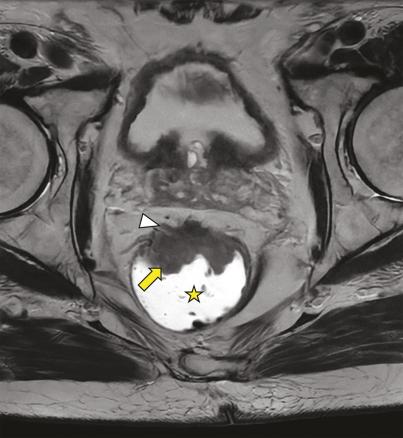

Adénocarcinome du moyen rectum chez un patient de 77 ans. Image axiale en pondération T2 d’une IRM rectale montrant une lésion tissulaire antérieure du moyen rectum (flèche) avec envahissement du mésorectum (T3) et spicules (tête de flèche) en regard des vésicules séminales.